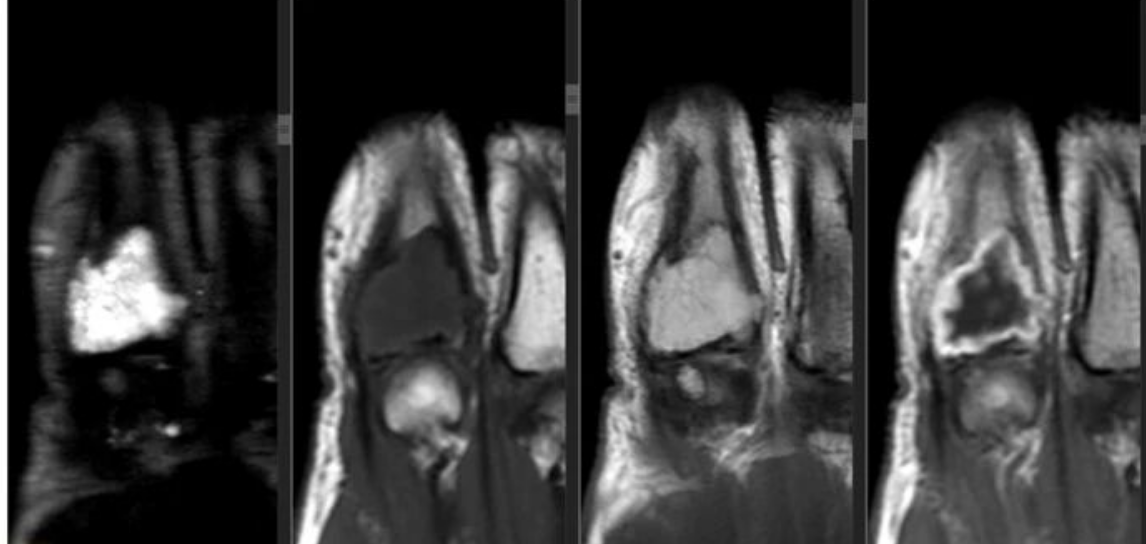

T2: AX/SAG T1/STIR: COR

右侧股骨上段骨髓腔内见椭圆形稍长T1、稍长T2信号影,大小约5.76cm×2.01cm×1.63cm;信号欠均匀,边缘尚清晰,周围骨皮质未见明确异常改变。所示髋肌及大腿肌各群形态及信号未见异常。

未钙化的瘤软骨T1WI呈低信号,T2WI呈明显高信号,增强可见不均匀环形强化